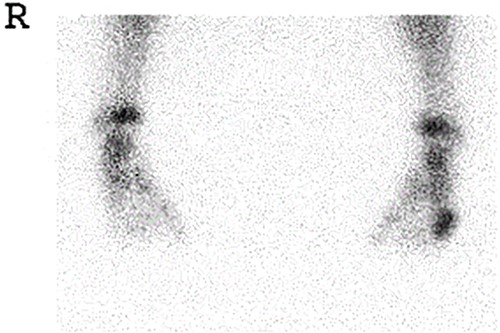

A 21-month-old Japanese female infant presented with a swollen mass on the dorsolateral aspect of the left foot. Her parents noticed the mass and brought the patient to our hospital. The patient had no past medical histories or complications prior to the occurrence. In addition, she received the BCG vaccine at the age of 4 months in Japan. At first visit to our hospital, physical examination revealed the ~3 × 3 cm mass was located on the dorsolateral aspect of the left foot and was hard accompanied by local heat (Fig. 1). Plain radiographs of the left foot showed a lytic lesion without periosteal reaction in the fifth metatarsal bone (Fig. 2). Magnetic resonance imaging (MRI) showed an isointense lesion on T1-weighted images and a hyperintense lesion on T2-weighted images around and within fifth metatarsal (Fig. 3). Gallium scintigraphy revealed intense uptake in the patient’s left foot (Fig. 4). In addition, laboratory examination was within normal. Based on medical history, clinical and imaging findings, we considered the possibility of neoplasia or osteomyelitis and performed an open debridement and biopsy of the lesion to make a diagnosis. The lesion was yellow and consisted of weak, adipose-like tissue that surrounded and continued into the inferior of the fifth metatarsal bone (Fig. 5). The lesion inside and outside the bone was resected as much as possible. Histopathologic examination of the lesion showed granulomatous inflammation including anaplastic giant cells, Langerhans-type giant cells and caseous necrosis (Fig. 6). Based on these results, TB or BCG osteomyelitis was considered as a diagnosis. The tuberculin test was positive, but the QuantiFERON TB test was negative. In addition, samples analyzed using polymerase chain reaction did not identify M. tuberculosis, but did identify the BCG Tokyo-172 strain. Per these findings, the patient was diagnosed with BCG osteomyelitis of the fifth metatarsal and oral treatment with anti-TB medicine including isoniazid (100 mg/day) and rifampicin (150 mg/day) was started. Clinical findings included reduction in swelling of the mass and gradual remodeling of the lytic lesion of the fifth metatarsal on plain radiographs (Fig. 7). However, 10 months after starting the anti-TB treatment, the mass recurred, and MRI revealed a residual high-intensity lesion around and inside the fifth metatarsal on T2-weighted fat-suppressed images (Fig. 8). It was determined that the lesion was difficult to control with anti-TB treatment alone, so an open debridement for the lesion was performed again. Histopathologic examination of the lesion revealed an epithelioid granuloma with necrosis. Therefore, the anti-TB treatment was continued. Six months after the second surgery, clinical and radiographic image findings showed complete improvement (Fig. 9). As a result, anti-TB treatment was ended. At the time of writing this report, 8 years after starting anti-TB treatment, there has been no recurrence.

Gallium scintigraphy revealed intense uptake in the patient’s left foot.